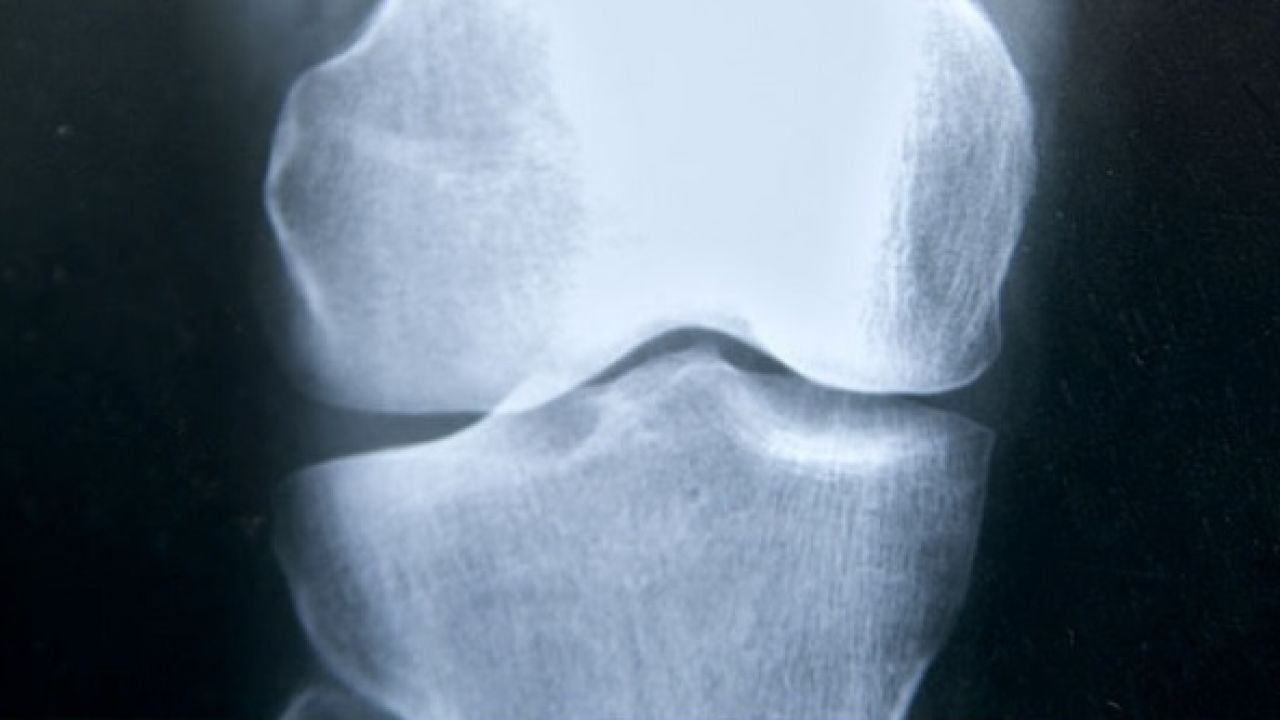

La similitud de sus síntomas con los de otras dolencias óseas, como la osteoporosis, hace que el protocolo de detección sea de gran importancia, ya que muchas veces "se confunde". "Hay que pensar en ella para detectarla", dice la endocrinóloga. Además, la sistomatología es muy variable y depende de la "gravedad de la afección". Mayoritariamente consiste en "alteraciones en el esqueleto", explica Pérez. Las deformidades en los huesos, fácilmente fracturables, y la lenta velocidad de crecimiento en niños afectados son algunos de los síntomas de la enfermedad.

"Es mucho más grave en niños que en adultos", explica la doctora. En los fetos puede provocar "dificultades en la formación del cráneo y problemas respiratorios". Cuánta más edad se tenga, menor es la gravedad de la enfermedad, ya que "ha dado tiempo a que los huesos se formen", aunque sigue habiendo riesgo de "fractura fácil" por esa desmineralización. En cuanto al tratamiento, actualmente existe uno que consiste en la sustitución de la proteína fosfatasa alcalina, aunque aún se están realizando ensayos clínicos.